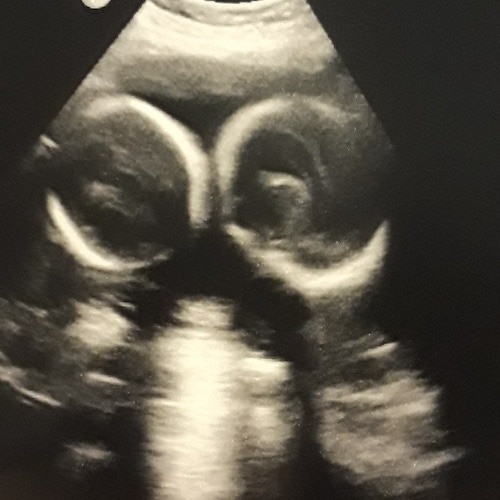

- Ultrasound Photos at 24 Weeks Pregnant With Twins

Ultrasound Photos at 24 Weeks Pregnant With Twins